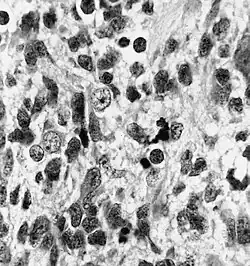

Histologically, medulloepithelioma resemble a primitive neural tube and with neuronal, glial and mesenchymal elements.[8][9] Flexner-Wintersteiner rosettes may also be observed.[10]

Immunohistochemically, neural tube-like structures are vimentin positive in the majority of medulloepitheliomas.[11] Poorly differentiated medulloepitheliomas are vimentin negative.